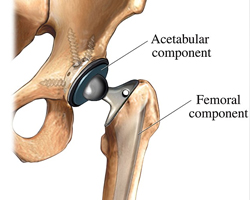

During a hip replacement operation, the surgeon removes damaged cartilage and bone from your hip joint and replaces them with new , man-made parts.

The hip joint is made up of the interconnection of two bones in a ball and socket:

1) the socket in the pelvis (acetabulum), 2) the ball (femoral head). Hip fractures refer to the femur fracture.